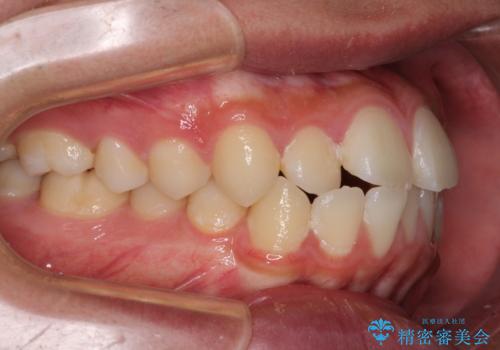

- 前歯のデコボコと口元の突出感を気にして来院された患者様です。

上下前歯がくちばしのように突出していたため、上下左右の第一小臼歯4本を抜歯し、ワイヤー装置にて矯正治療を行うこととしました。

左上は第二小臼歯が90度捻れており、状態が良くない歯であったため、左のみ第二小臼歯を抜歯することとしました。

上顎骨に対して下顎骨がやや前方位に位置しているため、下顎前歯をあまり内側に移動させることができず、口元の突出感改善は期待以上にはならないと予測しておりましたが、満足いくの引っ込み具合となりました。